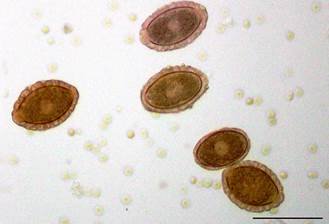

E o Platynosomum fastosum fica alojado no duto biliar do gatinho.